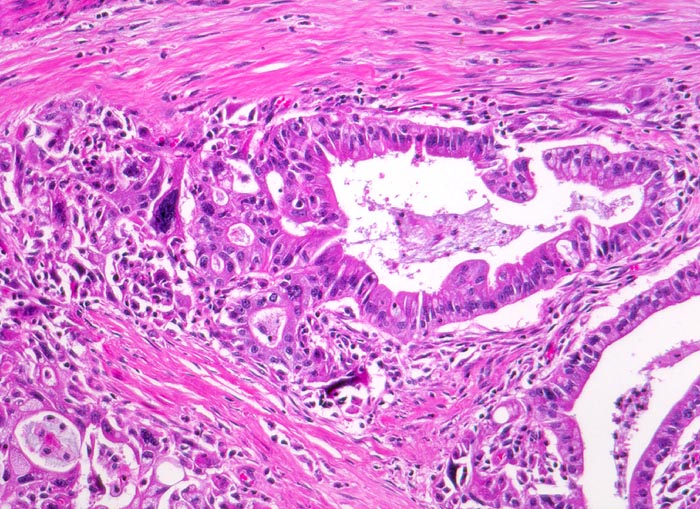

Die meisten Pankreaskarzinome sind mässig bis hoch differenziert und führen zu einer deutlichen desmoplastischen Stromareaktion (derbe Konsistenz). Hochdifferenzierte Tumoren (> 1502) können sehr ähnlich aussehen wie eine chronische Pankreatitis (> 4243). Im Gegensatz zur Pankreatitis sind die neoplastischen Drüsen verformt oder rupturiert und zeigen zelluläre Atypien (grosse polymorphe Kerne mit prominenten Nucleolen). Die Tumordrüsen sind unregelmässig im Stroma angeordnet und nicht lobulär wie in der Pankreatitis. Nicht selten ist eine Nervenscheideninvasion nachweisbar (> 5884). Gelegentlich zeigen die Gänge im tumorfreien Parenchym dysplastische Veränderungen oder der Tumor breitet sich intraduktal entlang des Pankreasganges aus.

• Unregelmässige Anordnung der Drüsen (keine Läppchenarchitektur erkennbar).

• Inkomplette Drüsen mit unvollständigen Lumina und Infiltration des Stromas durch Tumoreinzelzellen.

• Desmoplastisches Stroma.

• Rechts oben Reste von nicht neoplastischem Pankreasparenchym mit fokaler chronisch obstruktiver Pankreatitis als Folge von tumorbedingten Gangobstruktionen: Vollständige Atrophie des exokrinen Pankreas bei erhaltenen Inseln. Ersatz des atrophen Parenchyms durch Fibrose. Chronisches Entzündungsinfiltrat.